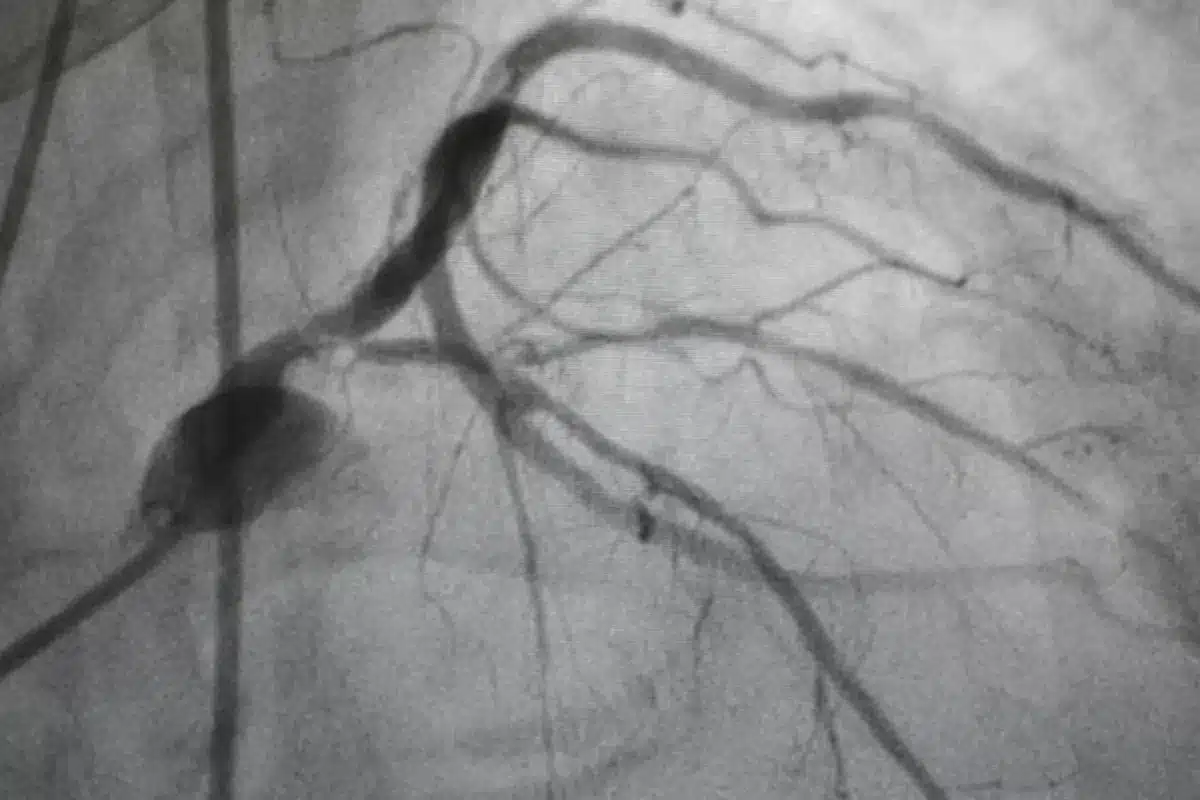

Coronary Angiography

Before a doctor recommends an invasive procedure like coronary angiography, they typically gather a substantial amount of evidence. An angiogram is the final, definitive test, but it is rarely the starting point. The diagnostic journey usually begins with simpler, noninvasive checks to assess the likelihood of heart disease. These preliminary tests act as a screening process, filtering out patients who may have muscle pain or indigestion from those who truly have blocked arteries.

This step-by-step approach guarantees that patients only undergo invasive procedures when absolutely necessary. It also helps the medical team plan the angiogram. For example, if a stress test shows a problem in the back of the heart, the doctor knows exactly where to look during the catheterization. Understanding this sequence of testing helps patients see the big picture and understand why they might need several appointments before the “big test” occurs.